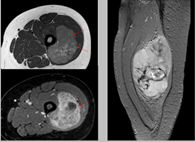

Se usa una amplia gama de técnicas de adquisición de imágenes para poder ver dentro del cuerpo y determinar el alcance de un sarcoma óseo y establecer la presencia o ausencia de enfermedad metastásica distante.

1. Rayos X

2. Resonancia magnética

3. TAC contrastado

Pruebas de imágen

Las pruebas de diagnóstico por imágenes utilizan ondas sonoras, rayos X, campos magnéticos o sustancias radiactivas para crear imágenes del interior del cuerpo. Las pruebas de diagnóstico por imágenes pueden realizarse por diversos motivos, como:

Las imágenes más representativas o más comunes son:

1. Radiografías de tórax

2. Ultrasonido

3. Tomografía Computarizada

4. PET scan

5. Resonancia Magnética